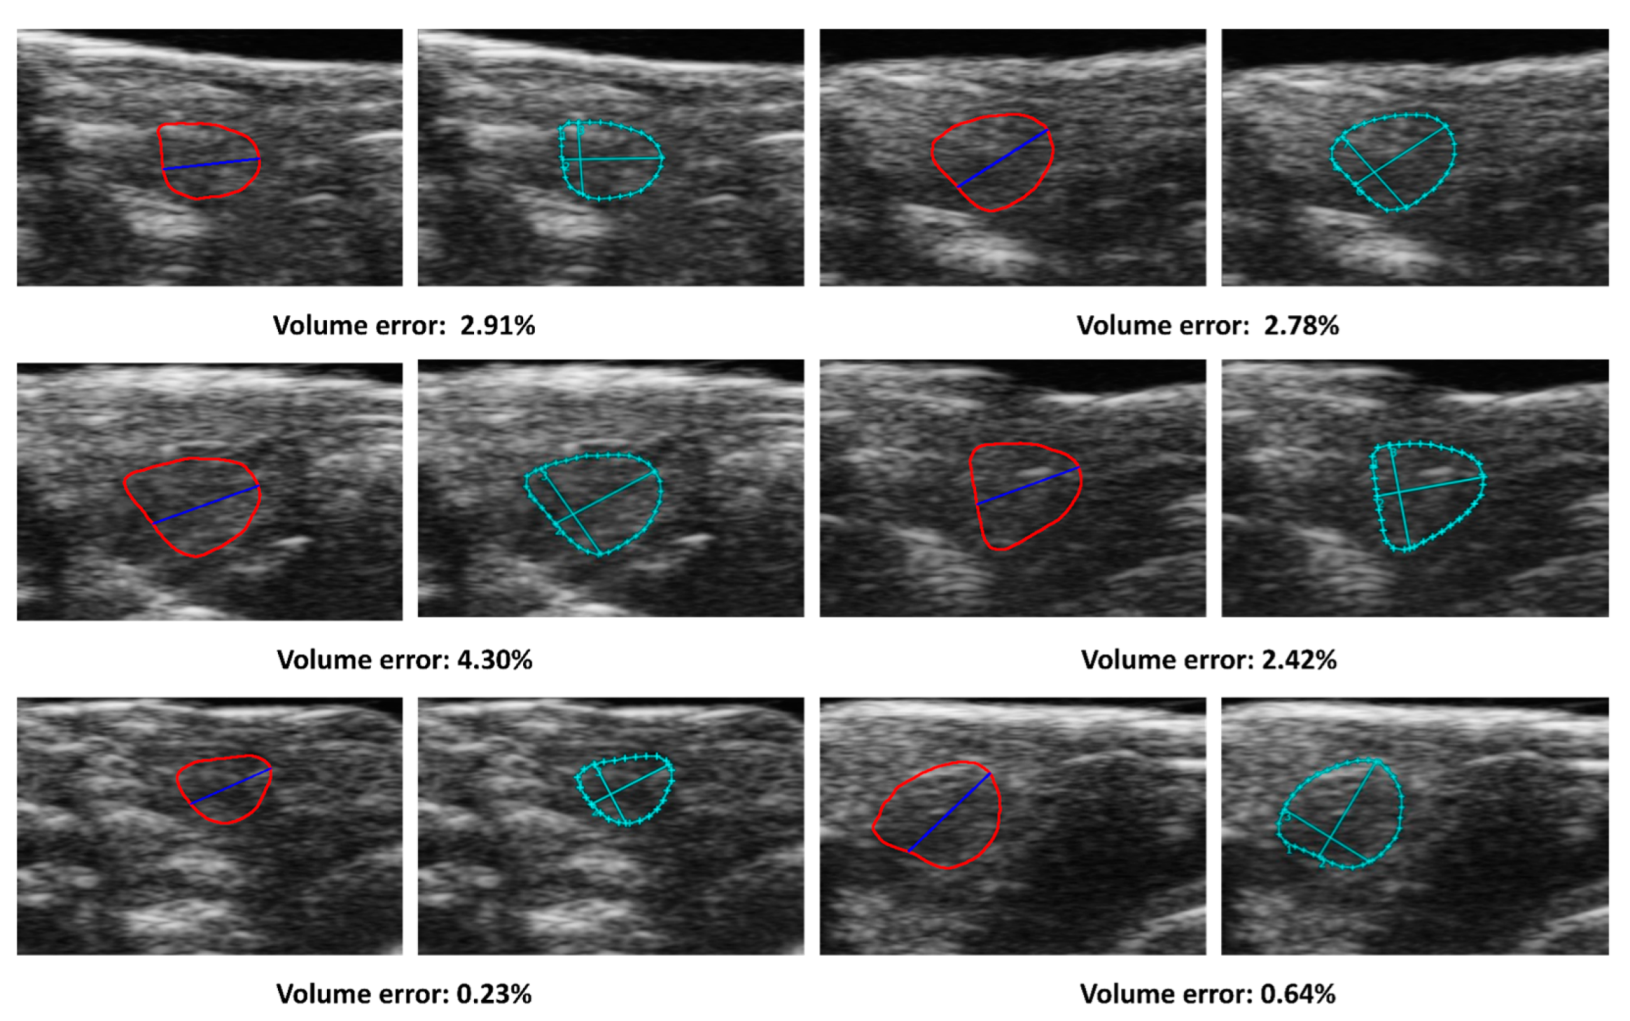

The present study aimed to develop a method for automatically calculating ejection fraction (EF) in fish populations using image processing techniques (Figure 6). The method’s performance was evaluated by comparing its results with manual assessments of the EF by three experienced biologists. The methodology involved detecting the ventricle area and subsequently measuring its size and the left axis length (LAX) from selected frames. A set of 51 videos containing three groups of fish was utilized for the evaluation, with manually labeled frames being chosen for the analysis. The obtained results indicated that the error rate ranged from 0.11% to 37.05% (Figure 7). Results from our automatic EF evaluation are consistent with manual measurements by each of the three biologists. A significant reduction of cardiac function in the AIC model can be detected (Figure 8). Notably, the average error was 9.83%, indicating the high accuracy of the automatic EF evaluation. The study reveals that the proposed method is promising to enhance the efficiency and accuracy of EF calculation in zebrafish.

Figure 6.

Comparison of automatic and manual volumes measurements. The solid lines in the figure corresponded to the ventricle contour and the LAX and detected by the proposed method. The cropped images, labeled manually with dotted lines, correspond to the manual label for each frame. The figures in the same row were selected from the same fish group, and the measurements are in pixels.